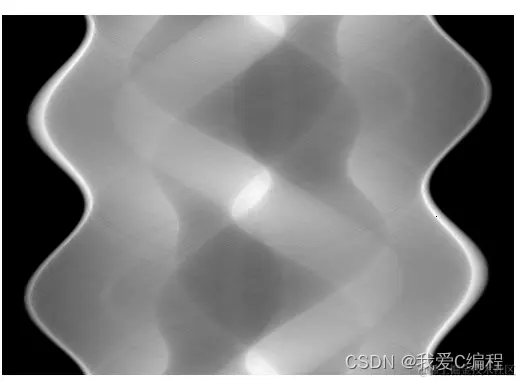

1.png

上图应可以清晰的描述傅立叶中心切片定理的过程:对投影的一维傅立叶变换等效于对原图像进行二维的傅立叶变换。傅立叶切片定理的意义在于,通过投影上执行傅立叶变换,可以从每个投影中得到二维傅立叶变换。从而投影图像重建的问题,可以按以下方法进行求解:采集不同时间下足够多的投影(一般为180次采集),求解各个投影的一维傅立叶变换,将上述切片汇集成图像的二维傅立叶变换,再利用傅立叶反变换求得重建图像。